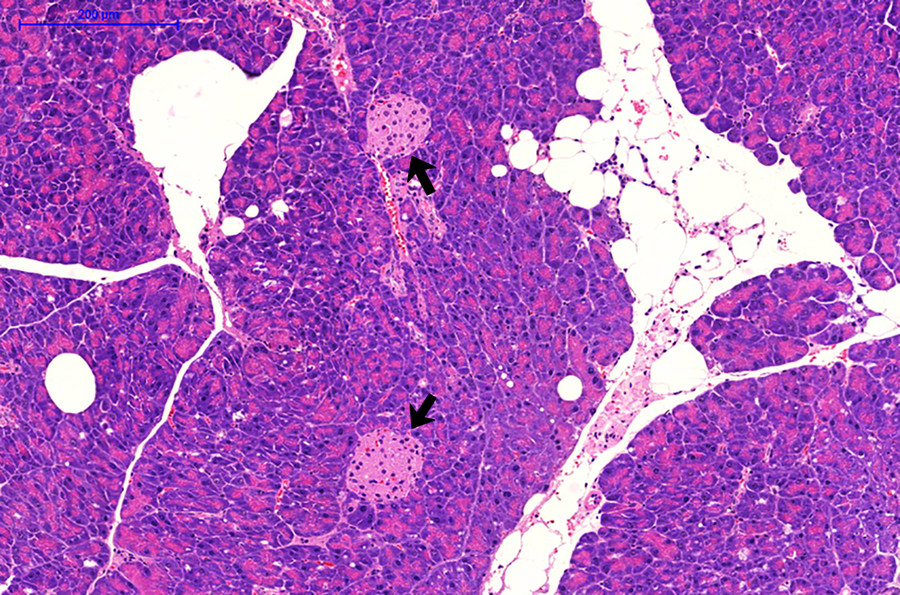

Um herauszufinden, wie Fettzellen die Funktion der Bauchspeicheldrüse beeinträchtigen könnten, isolierten die Wissenschaftlerinnen und Wissenschaftler um Schürmann und Schulz erstmals Fett-Vorläuferzellen aus der Bauchspeicheldrüse von Mäusen und ließen sie zu reifen Fettzellen ausdifferenzieren. Wurden die reifen Fettzellen anschließend zusammen mit den Langerhans-Inseln** der Bauchspeicheldrüse kultiviert, setzten die Beta-Zellen der „Inseln“ verstärkt Insulin frei. „Wir vermuten, dass durch die erhöhte Insulinfreisetzung die Langerhans-Inseln von diabetesanfälligen Tieren schneller erschöpfen und nach einiger Zeit ihre Funktion ganz einstellen. Auf diese Weise könnte Fett in der Bauchspeicheldrüse zur Entstehung des Typ-2-Diabetes beitragen“, sagt Schürmann.

** Die Langerhans-Inseln – auch als Inselzellen oder Langerhans‘sche Inseln bezeichnet – sind inselartig eingebettete Ansammlungen hormonbildender Zellen in der Bauchspeicheldrüse. Ein gesunder Erwachsener hat etwa eine Millionen Langerhans-Inseln. Jede „Insel“ hat einen Durchmesser von 0,2-0,5 Millimeter. Die Beta-Zellen stellen das blutzuckersenkende Hormon Insulin her und machen etwa 65 bis 80 Prozent der Inselzellen aus. Sie geben bei erhöhten Blutzuckerspiegeln Insulin ins Blut ab, damit sich diese wieder normalisieren.